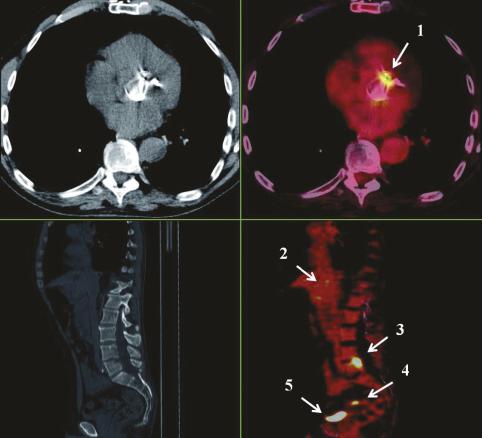

Imagerie TEP (à droite) couplée à un scanner thoraco- abdomino-pelvien (à gauche). Extrait de : Endocardite infectieuse